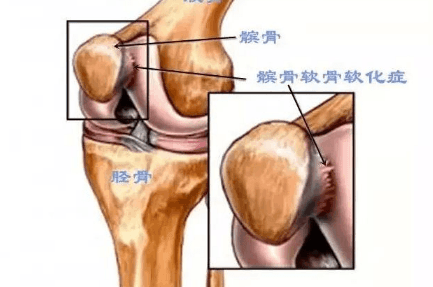

╯0╰ 儿童膝关节滑膜炎病因及治疗方法大揭秘!住院周期短等明显优势,在某些疾患中己逐步取代传统开放手术的趋势。 得益于关节镜技术在成人群体中的推广及发展,医护工作者对儿童膝关... 对各种不同类型的滑膜炎的显影无明显特异性。此外,MRI检查价格昂贵。 儿童膝关节滑膜治疗 药物治疗 目前治疗膝关节滑膜炎尚无特效药物...